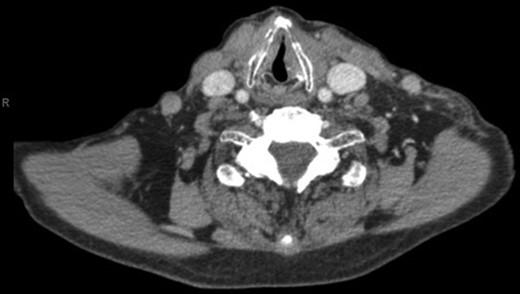

With a working differential of parapharyngeal space infection and possible malignancy, the patient was referred for a computed tomography (CT) scan of the neck and thorax with contrast. The patient was also started empirically on intravenous co-amoxiclav as treatment for neck space collection. CT imaging, performed 24 h after admission, revealed no evidence of malignancy or indeed any paraphayrngeal space collection. Few small lymph nodes were noted on the left side of the neck, but were deemed to be reactive in nature, and left vocal cord palsy was evident (Fig. 1). The key finding was that of a left sternoclavicular joint collection and closely associated superficial anterior chest wall, soft tissue swelling and oedema (Fig. 2). This inflammatory process was also noted deep to the manubrium and sternum and extending somewhat into the mediastinum with evident enlarged mediastinal lymph nodes (Fig. 3). The CT findings were in keeping with SSA with associated superficial and deep tissue inflammation and oedema. With no other cause found, the vocal cord palsy was attributed to the inflammation within the mediastinum, which in turn was caused by superficial burn from hot water bottle use.

Computed tomography. A 67-year-old male with SSA. Findings: left sternoclavicular joint collection and closely associated superficial anterior chest wall, soft tissue swelling and oedema. The oedema can be seen to be spreading into the chest. Technique: contrast-enhanced axial CT of the neck and thorax.